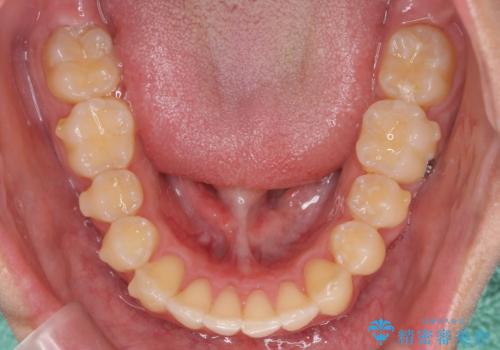

過蓋咬合・上顎前突・叢生を改善するマウスピース矯正

- 前歯のがたつき、不揃いさの改善を求めて来院されました。

・前歯の深い噛み合わせ (過蓋咬合)

・上顎前突(Angle Class2)

・叢生(がたつき)

以上のような問題点をマウスピース矯正インビザラインとマイクロインプラントを用いて矯正治療を行い改善して行きます。

20時間以上のマウスピース装着、ゴムかけを遵守していただいたおかげでしっかりと噛み合わせ、がたつきの改善を行うことができました。